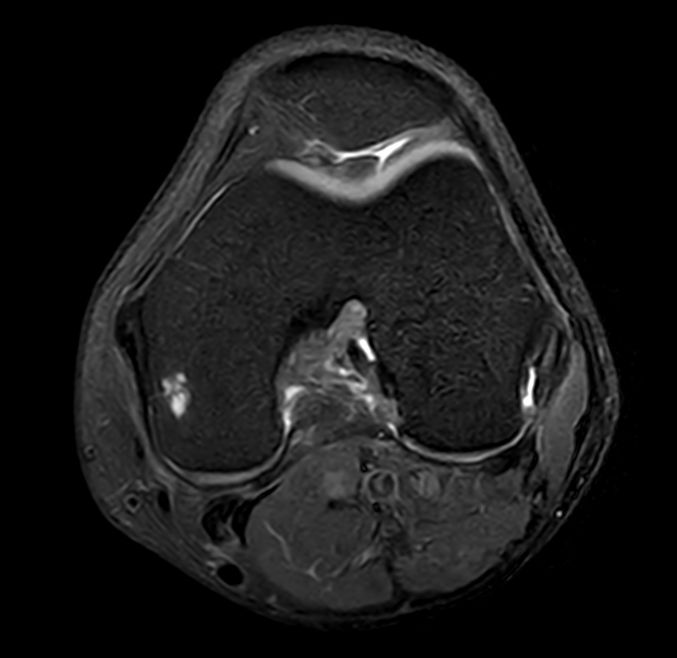

Axial T1w TSE